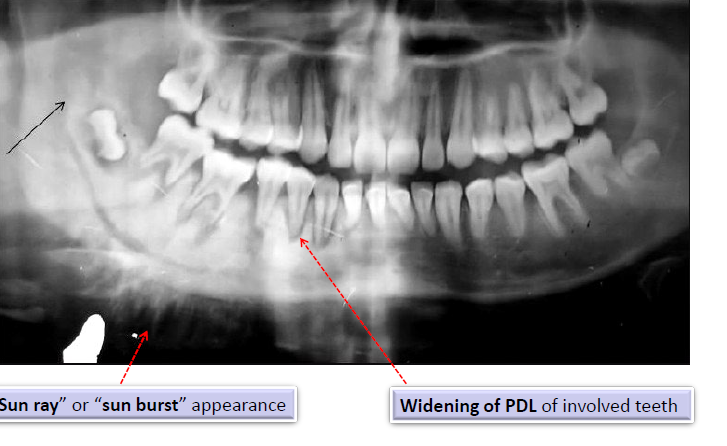

osteosarcoma radiographic features

“sun ray” or “sun burst” appearance

widening of the PDL of involved teeth

radiographic features of metastatic tumors of the jaws

usually poorly-defined and radiolucent

radiopaque

sun-ray or sun-burst appearance

radiographically, osteosarcoma of the jaws may show